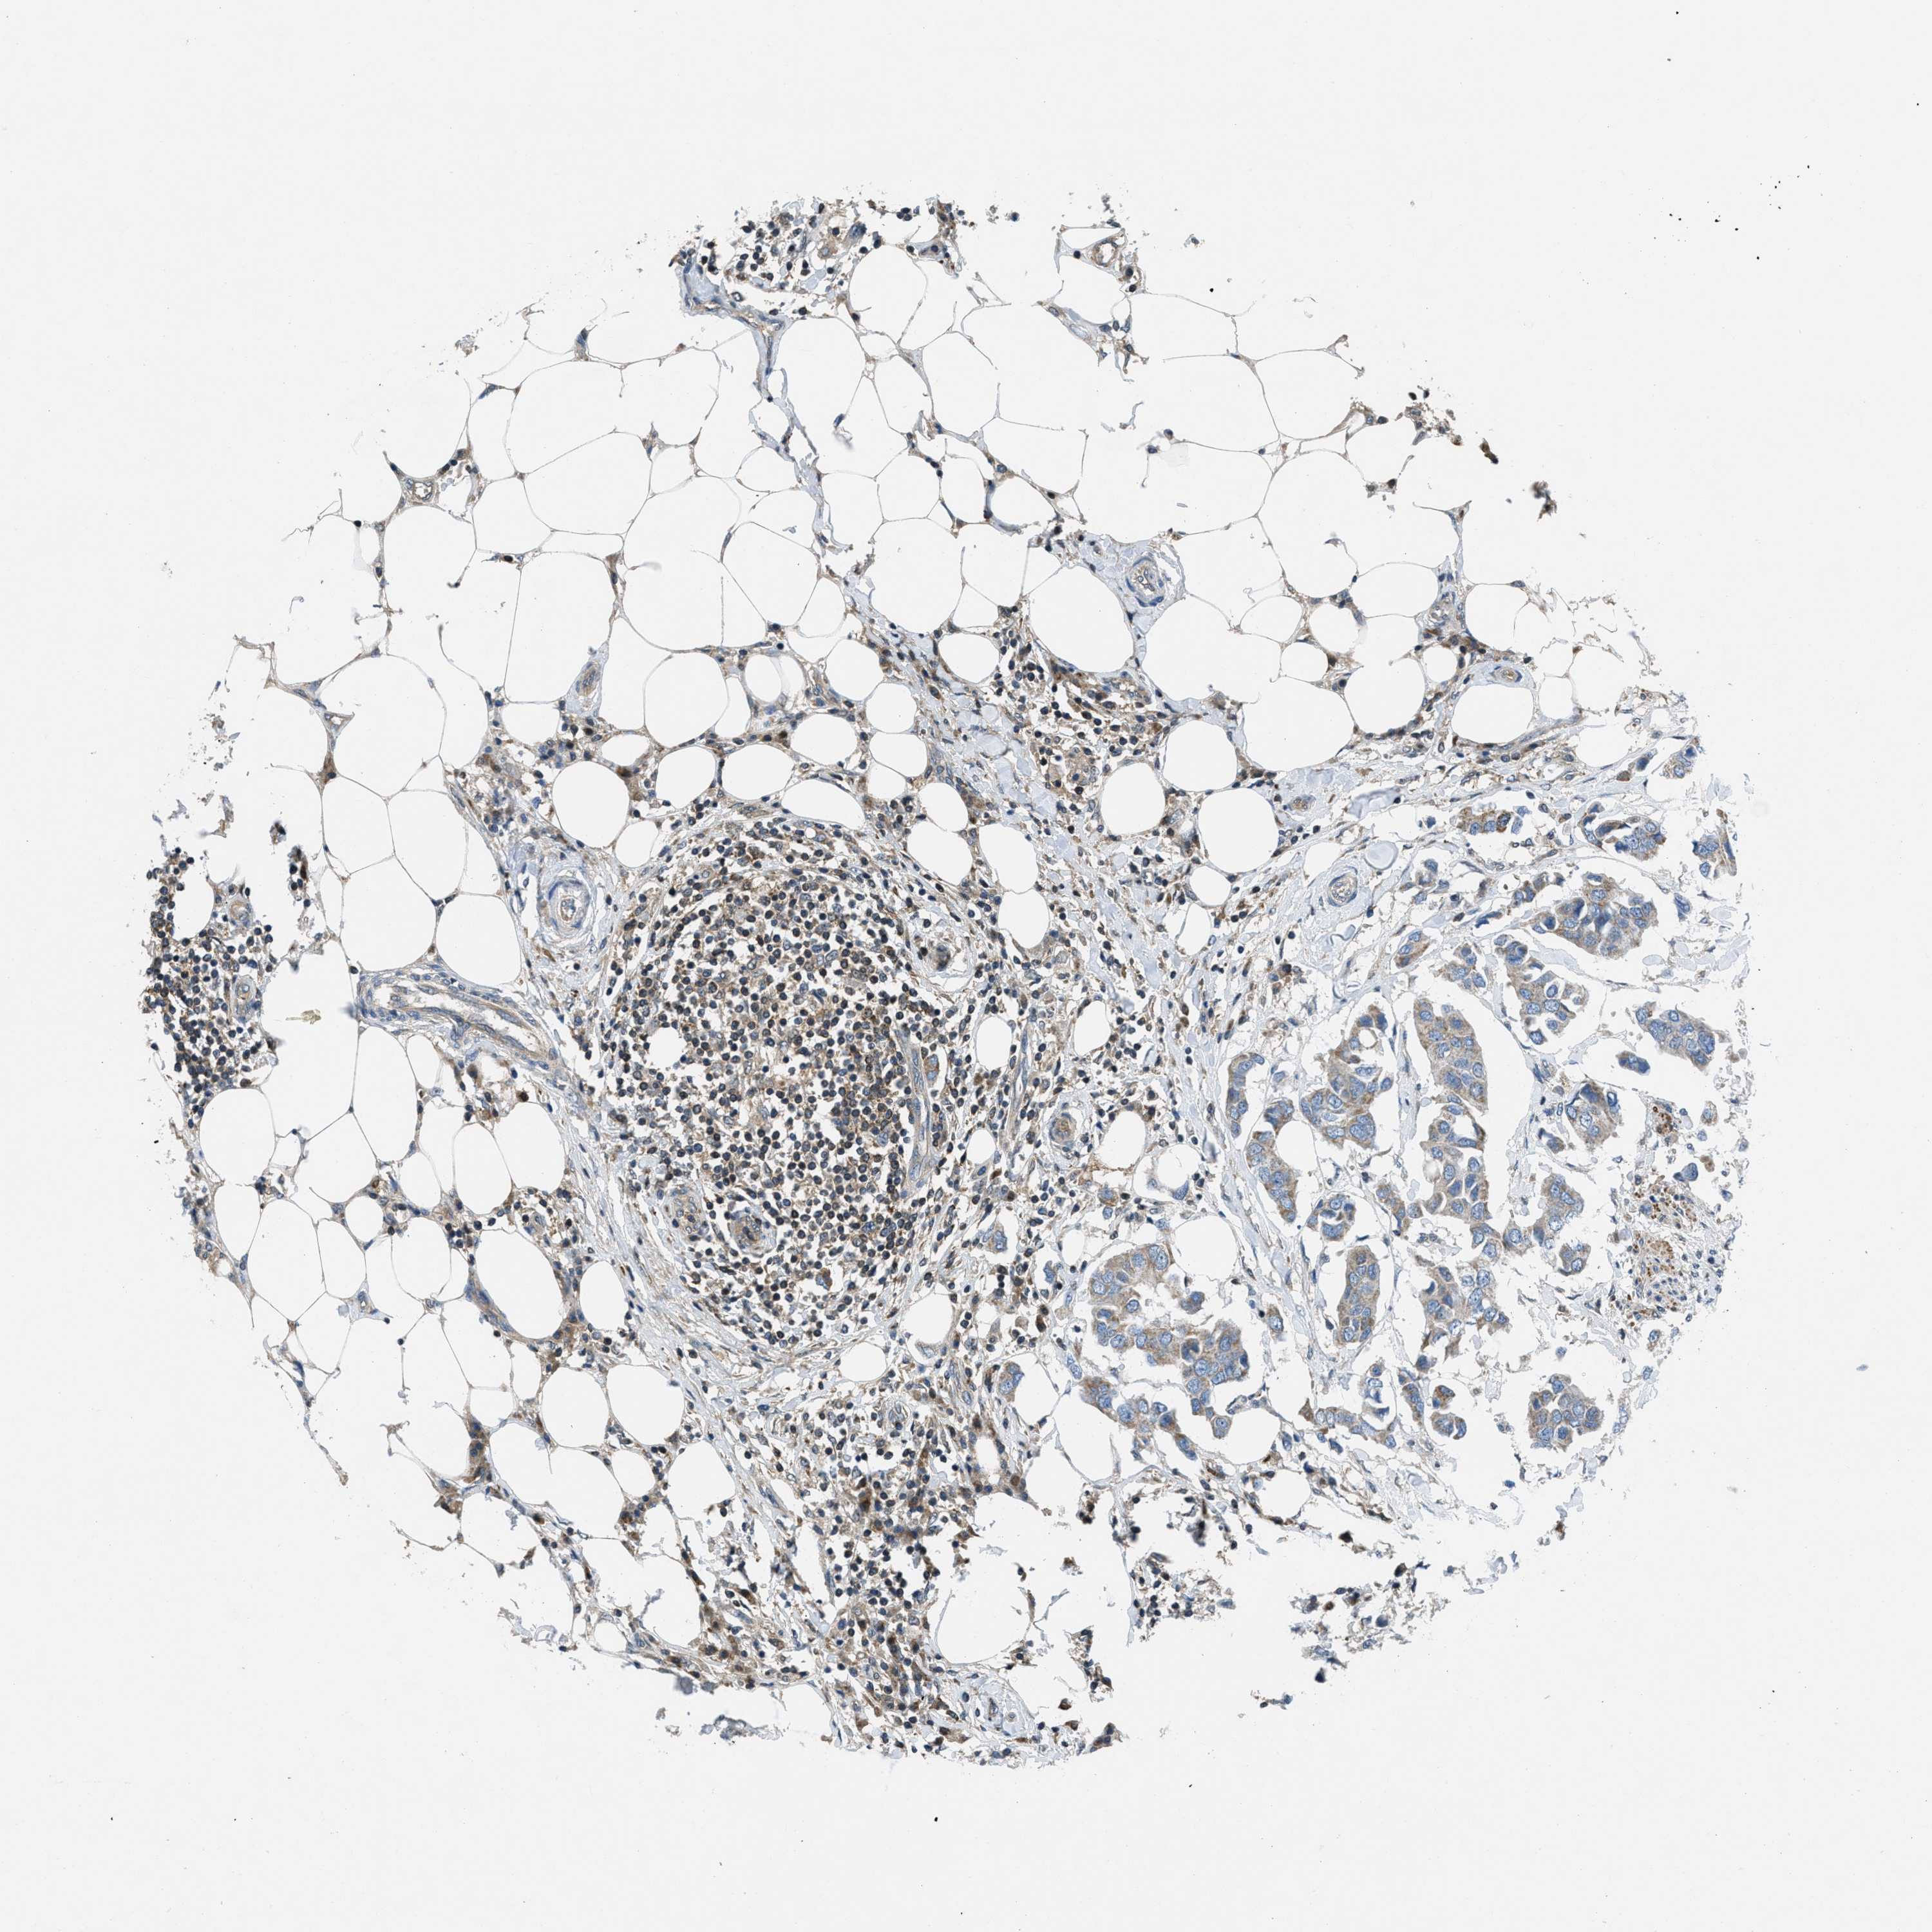

CANCER BREAST CANCER Show tissue menu

BRCA TCGA BRCA VALIDATION PROTEIN EXPRESSION